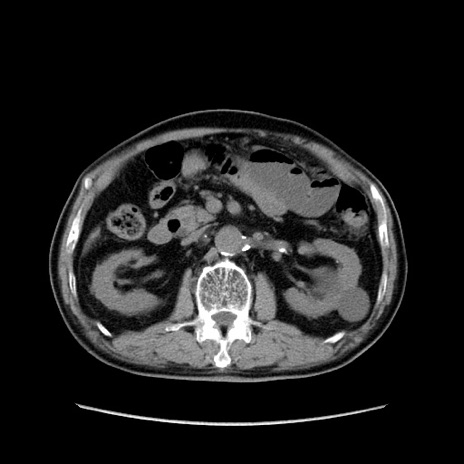

症例24(横断像)

【症例】80歳代男性

【主訴】左側腹部痛、嘔吐

【現病歴】本日早朝より左腹部に痛みあり。昼頃嘔吐認めたため、救急要請。

【既往歴】直腸癌(Mile手術)、胆摘

【身体所見】意識清明、BT 35.9℃、BP 221/93mmHg、SpO2 97%(RA) 、腹部:左ストーマ周囲に限局性の腹部膨隆あり。 膨隆部自発痛・圧痛あり・軟。

【データ】WBC 7700、CRP 0.09